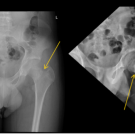

Lana Soylu, MD, FAAP; Cole R. Fiedler, BS

A 13-year-old boy presented to his pediatrician’s office with a 1-day history of left hip pain. The patient reported that he felt a sharp pain in his anterior left hip while running, causing him to limp. He...